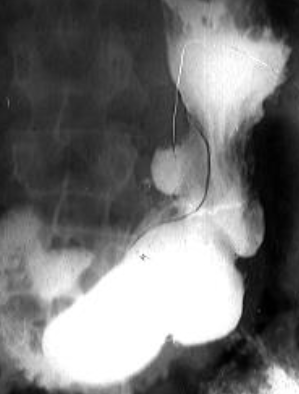

Volvulus gastric